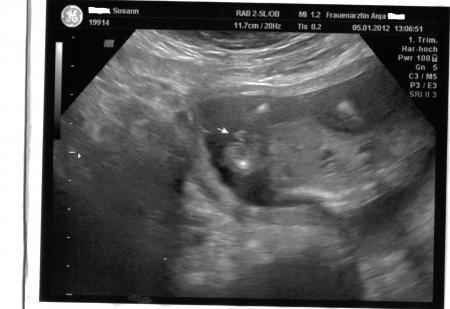

Hallo Ihr lieben, nach dem ich mit Termin heut 3 STUNDEN !!!warten musste habe ich noch erfahren das Sie keinen Ultraschall macht ok dachte ich mir dann Bezahle ich halt hauptsache ich seh mein Baby Gesagt getan meinem Baby geht es super es hat Geschlafen aber sowas von Süss das glaub ihr garnicht. Er ist 9,5 cm "groß" und 104 gramm "schwer". Sie hat auch noch mal gesagt das er (warscheinlich) ein Junge wird. ich bin heute 15+0 ssw laut untersuchung 15+2 ssw. Ach Mädels ich freu mich so das mit meinem Baby alles ok ist aber ein wehmutstropfen gab es noch ich habe 1,6 kg zugenommen ich habe gefragt ob das ok ist und sie sagte ja beim 2 kind nimmt man schneller zu na toll das macht mut so jetzt möchte ich euch nicht weiter stören. ich hänge euch noch die Bilder von heute an lg und einen schönen abend

Bild zu Bericht vom Frauenarzt + Fotos - Forum für Juni - Mamis

Super das freut mich das alles In Ordnung ist,ja mann sieht auf dem Bild das es eindeutig ein Junge ist. Ich freue mich sehr für dich...... Liebe Grüße Melanie